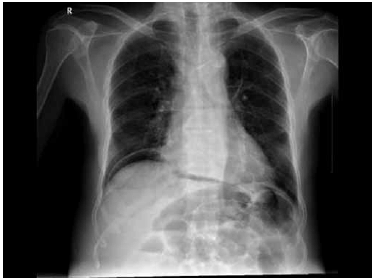

Homem de 38 anos dá entrada no pronto-socorro, referindo forte dor em todo o abdome há duas horas, de início súbito, sem fatores de melhora. Há duas semanas, está em tratamento para úlcera no duodeno. Encontra-se consciente, descorado ++/++++, eupneico. PA: 90 x 40 mmHg; P: 98 bpm. Ao exame físico do abdome: plano, com resistência voluntária à palpação, DB + difuso, com sinal de Jobert presente. RHA + normais. Após as medidas de suporte clínico e coleta de exames laboratoriais, foi realizada radiografia simples de abdome (demonstrada a seguir).